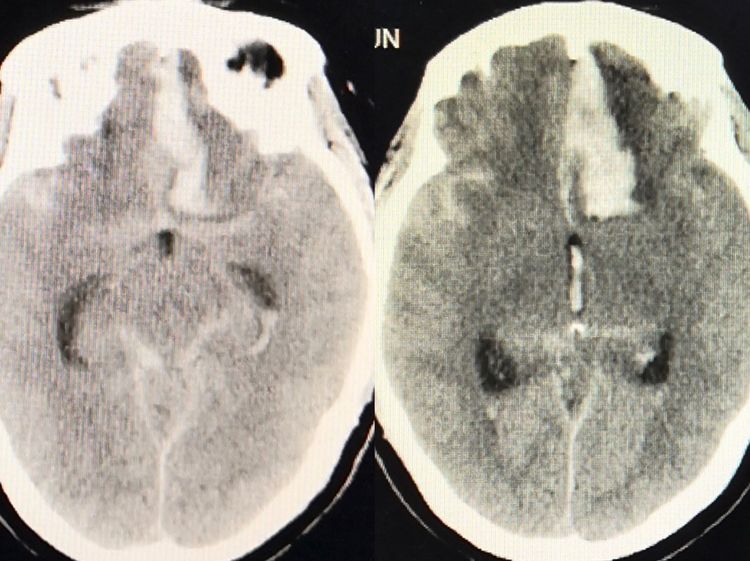

56岁女性,突发头痛,处于嗜睡状态。

当地医院CT显示蛛网膜下腔及脑室出血,伴有额底纵裂血肿形成。

行CTA检查,发现额底(与大脑前动脉关系密切)有动脉瘤样结构,初步诊断为前交通或大脑前动脉瘤。于是我应邀去会诊,准备好了动脉瘤栓塞。

当完成双侧颈内动脉造影后我们发现,不是最初的诊断;

居然是一个前颅窝的硬脑膜动静脉瘘,供血来于双侧眼动脉的脑膜组。

我们认为的动脉瘤其实是引流静脉的球形扩张!